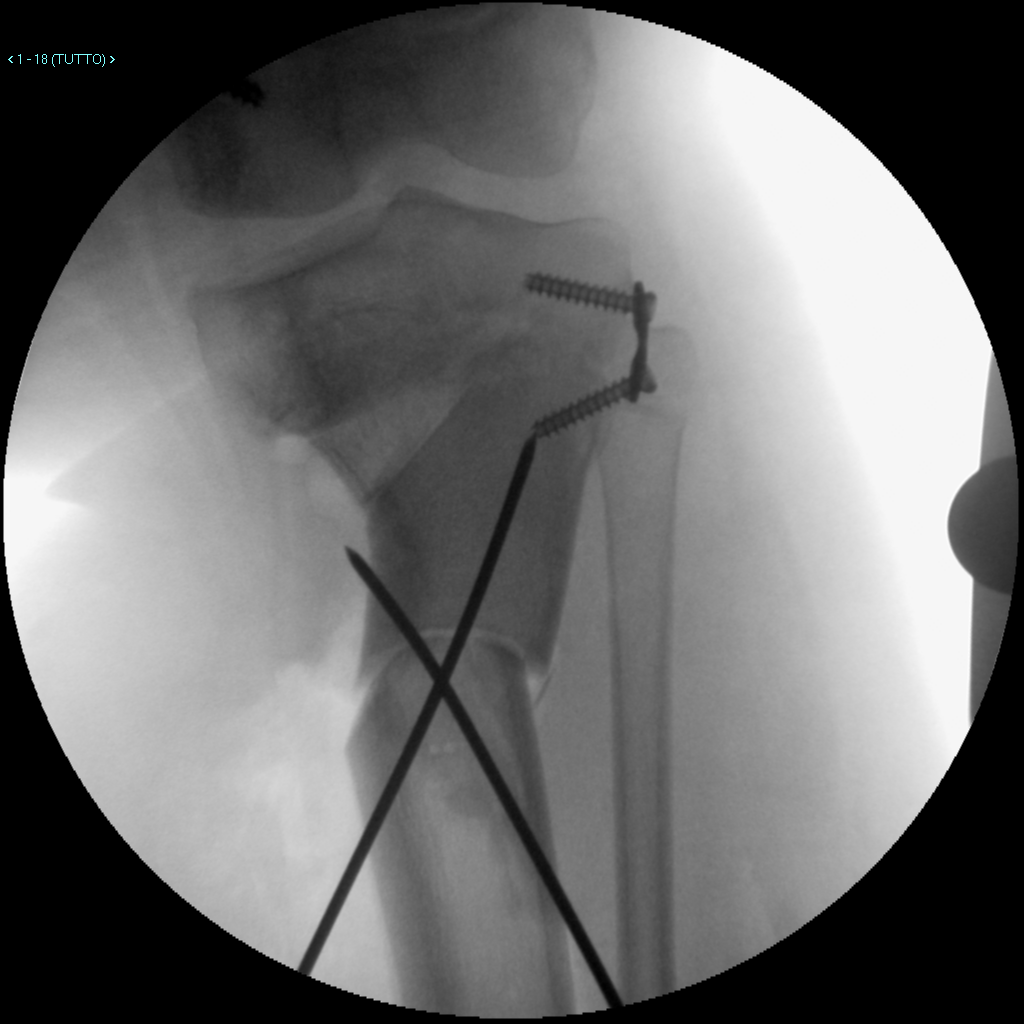

Qualora le deviazioni, idiopatiche o post-traumatiche, siano presenti in soggetti in crescita (in cui cioè è ancora presente attività della cartilagine di accrescimento o fisi) è possibile trattarle mediante un intervento chirurgico noto come epifisiodesi asim-metrica temporanea (Fig.2-3). Tale intervento sfrutta il potenziale di crescita residuo per “guidare” lo sviluppo favorendo la correzione del valgismo o del varismo. Ciò avviene mediante l’utilizzo di placchette lunghe pochi centimetri posizionate a cava-liere della/e fisi in grado di modulare l’accrescimento in tale sede. L’intervento pre-vede solo una piccola cicatrice, è descritta ampiamente una buona tollerabilità al do-lore grazie anche all’utilizzo di un’anestesia generale combinata con una loco-regionale del sito chirurgico.

La dimissione è nei due giorni successivi all’intervento, nei quali il/la paziente è aiu-tato/a a riprendere la sua piena autonomia grazie alla riabilitazione operata dai fisiote-rapisti, mentre il pieno ritorno allo sport avviene nel giro di 35-60 giorni dall’intervento.

La rimozione della/e placca/e verrà stabilita dall’Ortopedico attraverso le visite di controllo nel post-operatorio, in quanto dovrà essere attuata in base alla fase di cresci-ta e al grado di correzione.